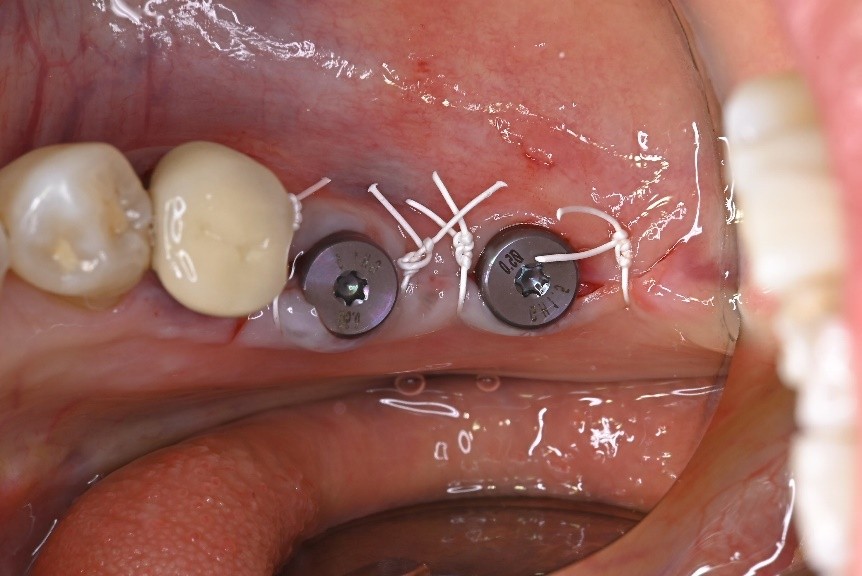

①治癒を左右する「縫合糸」へのこだわり

手術後の傷口を縫い合わせる縫合糸の選択は、感染リスクや歯ぐきの治癒の質を大きく左右します。安価な治療では、リーズナブルな「シルク糸」が使われがちですが、表面が粗く細菌が付着しやすいという懸念があります。

当院では安全と確実な治癒を最優先し、シルク糸の約10倍のコストがかかる高機能合成素材「ゴア糸(ePTFE)」を必ず使用しています。表面が滑らかで細菌が付着しにくく、術後の感染リスクを極めて低く抑えられるため、審美性が求められる薄い歯肉などの過酷な環境にも非常に適しています。

シルク糸を用いた症例写真

ゴア糸を用いた症例写真